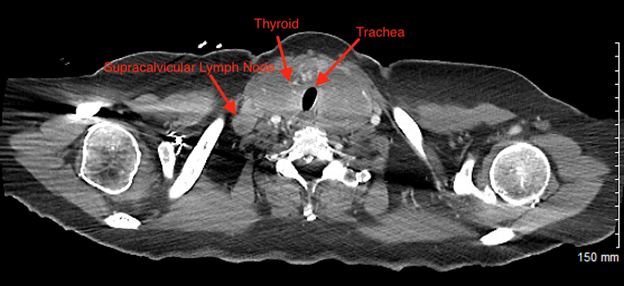

Patient underwent CT scan showing 19 mm x 6mm right supraclavicular lymph node (Figure 1) Large soft tissue mass in

Figure 1: 19 mm x 6mm

Right Enlarged Supraclavicular Lymph Node. Figure also shows positioning of

Trachea and Enlarged Thyroid.